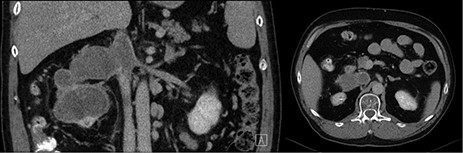

The detailed histopathology revealed a tumor of 10-cm maximum diameter, clear cell, with extensive areas of hemorrhage and necrosis, no evidence of lymphovascular invasion and no rhabdoid or sarcomatoid differentiation, negative surgical margins. The IVC thrombus was all formed of necrotic tissues with no active malignancy. Patient was decided to continue on Sutent after the recovery of surgery. One year follow-up showed no tumor recurrence and normal IVC without thrombus (Fig. 2).

Post-operative coronal and axial CT images showing free tumor bed and normal IVC.